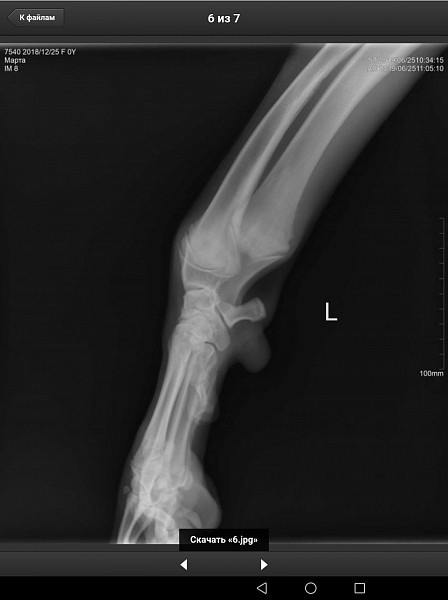

У нас немецкий дог, девочка, 6 месяцев, привита по возрасту. Поставлен диагноз Расслаивающий остеохондрит плечевого сустава (мышь плечевого сустава). Сказали, нужна операция по зачищению этого сустава. Как можно скорее.

Есть рентгеновский снимок. Прошу вас прокомментировать его, правильный ли диагноз? Как срочно нужно оперировать, если подтвердится диагноз? Какой период реабилитации? И, что нас ожидает в будущем, от чего могла развиться болезнь, наследственное это или нет, что делать, чтобы предупредить заболевание суставов других лап?

Здравствуйте. Судя по описываемым вами симптомам у собаки, действительно имеется поражения хрящевой поверхности какого-то сустава грудой конечности. На предоставленных вами снимках, затруднительно тщательно рассмотреть суставные поверхности. Ярко выраженной патологии хряща (расслаивающий остеохондрит не просматривается). Для подтверждения или исключения данной патологии наиболее оптимальным является компьютерная томография. При подтвтерждении диагноза, основным методом лечения является хирургическое вмешательство, направленное на устранение фрагментированного участка хряща и зачищении дефекта для формирования на месте поражения волокнистого хряща.